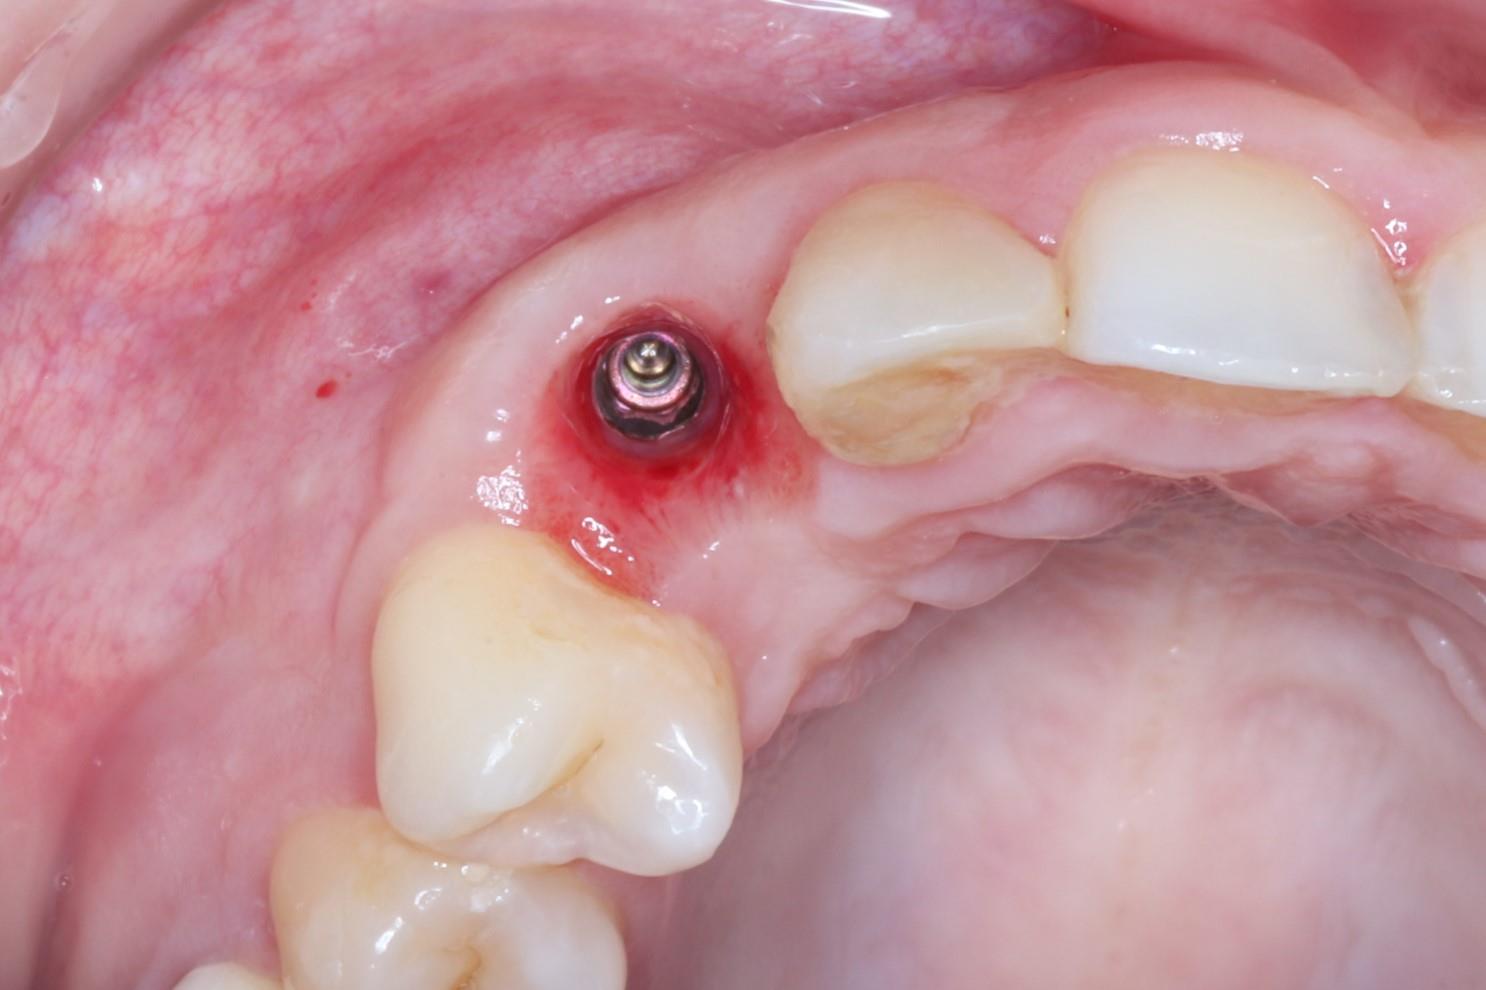

症例09

60代 男性 折れている歯を眠っている間に完全無痛でインプラントをして欲しい

治療後

| 主訴 | 折れている歯を眠っている間に完全無痛でインプラントをして欲しい。インプラント手術自体をいかに痛みや不安がなく治療ができる医院がないかを探していた。抜歯と同日のインプラント手術を「完璧にできる」という歯科医師に治療してもらいたいと思っている。 |

|---|---|

| 年代・性別 | 60代 男性 |

| 治療部位 | 左下7 |

| 治療費用 | インプラント手術料 300,000円 |

| 手術回数 | 2回 |

| 治療期間 | 4ヶ月 |

| 手術時間 | 90分 |

| 治療回数 | 5回 |